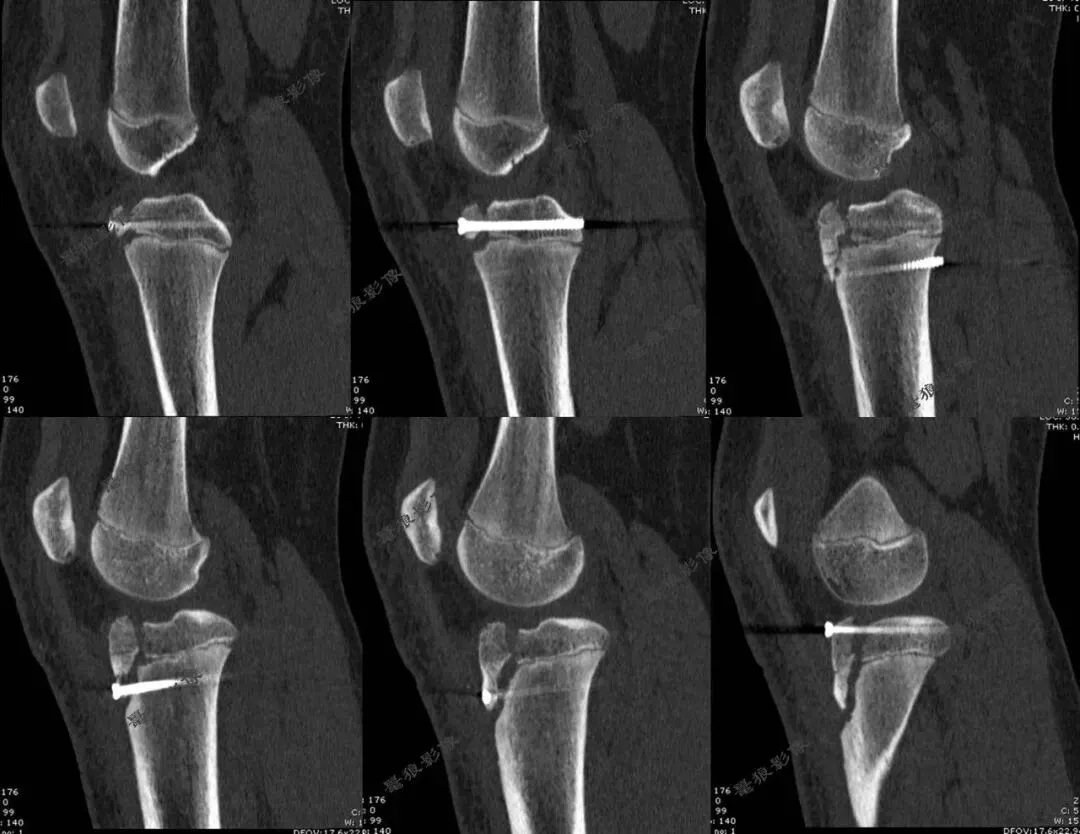

五.骨科主管医生如是说

1.常规手术:需要切开10-15cm左右切口才能复位骨折。缺点是:创伤大、疤痕大,且可能影响骨骺!

2.闭合复位手术:技术要求高,且要避开骨骺线进行固定,操作空间极小。本病例采用中医正骨+钳夹、顶棒推挤技术实现骨折闭合复位,仅3个长约0.5cm左右切口置入螺钉固定,完美复位并固定骨折。优点是:出血少、不留疤、康复快!

3.术后X线片:

4.术后CT: